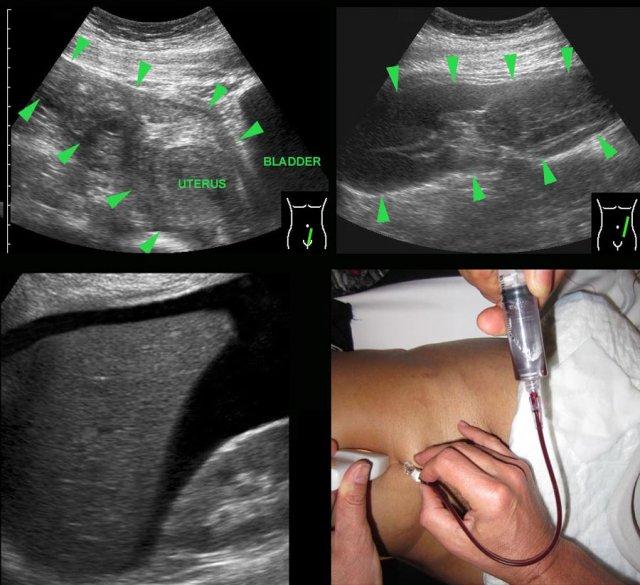

Các hình ảnh này của một phụ nữ trẻ bệnh nặng, đau nhiều với viêm phúc mạc toàn thể và CRP 250, nghi ngờ lâm sàng là thủng ruột thừa.

Siêu âm cho thấy ruột non mất nhu động (b.).

Không quan sát được ruột thừa.

TVUS cho thấy tử cung bình thường và buồng trứng bình thường (đầu mũi tên), được bao quanh bởi mô tăng âm (*).

CT xác nhận hình ảnh liệt ruột và ruột thừa bình thường (mũi tên).

PCR dương tính với lậu cầu.